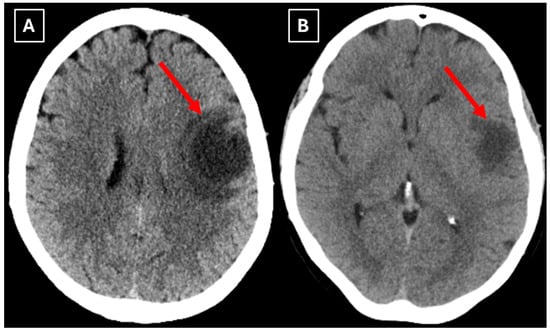

Two months later a follow-up head MRI was performed. It showed a substantial decrease in the volume of the lesion, no mass effect on the surrounding structures, and no perifocal edema (Figure 6 and Figure 7). No other demyelinating lesions were found in the cervical and thoracic spine MRI. The multiple sclerosis board recommended an MRI follow-up after six months as well as a clinical evaluation of the patient.

Figure 6. The 2-month follow-up MRI scan of the brain. In both (A): axial T2W axial sequence and (B): axial FLAIR, the mass has drastically decreased in size and has almost disappeared. A hyperintense demyelination focus can be seen subcortically in the basal parts of the left frontal lobe, which extends more into the white matter and has no mass effect on the surrounding structures. Red arrow—tumefactive demyelinating lesion.

Figure 7. The 2-month follow-up MRI axial scan of the brain. Previously seen peripheral rim-like diffusion restriction is resolved and there is residual minimal vasogenic edema on the axial trace image (A). (B): ADC map. (C): SWI sequence shows no evidence of a left frontal lobe mass but a prominent central traversing vein in the lesion site. (D): T1 postcontrast sequence shows minimal patchy contrast enhancement along the margin of the lesion. Based on the observed changes over the past 2 months, it is most likely that the findings correspond to a demyelinating lesion. Red arrow—tumefactive demyelinating lesion.

Finally, we provide a high-resolution MRI follow-up of two months’ duration showing near-complete regression of the lesion after corticosteroid therapy. The lesion decreased from 37.34 mm × 34.85 mm (AP × LL) to 24.87 mm × 29.71 mm following two weeks of corticosteroid therapy and after almost two months from the first MRI scan to minimal patchy contrast enhancement (Figure 7D). This marked decrease in the size of the lesion gives strong evidence that a demyelinating rather than neoplastic process is present.

Follow-up MRI showed lesion shrinkage after two weeks (Figure 4) and by two months, near-complete lesion regression and resolution of perifocal edema. The radiological course was typical for TDLs and no alternative differential diagnosis appeared reasonable, as both the clinical response to therapy and MRI follow-up strongly supported the demyelinating origin. Thus, biopsy was not performed in this case. In the literature similar cases have been reported where biopsy was avoided, as the disease responded to treatment and imaging findings were consistent with a demyelinating process [27]. Moreover, biopsy of the brain in TDLs carries considerable procedural risks, including seizures and post-operative infections [2]. However, despite the lesion regression after corticosteroid therapy, which was supportive of a TDL diagnosis, the lack of biopsy confirmation represents a limitation in this case and warrants explicit acknowledgment of the risk of misdiagnosis, especially with lesions that have less certain regression.